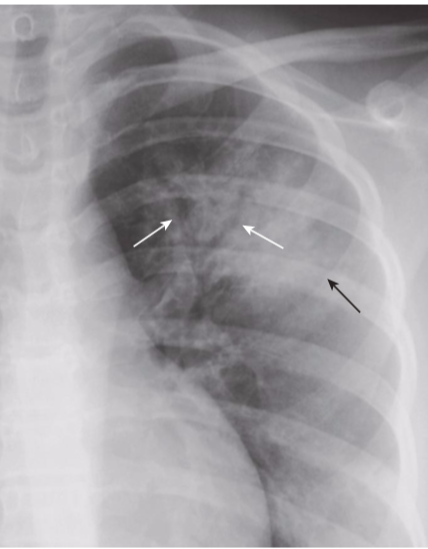

Hydropneumothorax.

hydropneumothorax produces an air-fluid level in the hemithorax marked by a straight edge and a sharp, air-over-fluid interface when the exposure is made with a horizontal x-ray beam (black arrows). This person was stabbed in the right side and there is a moderately large pneumothorax as shown by the visceral pleural white line (white arrows).